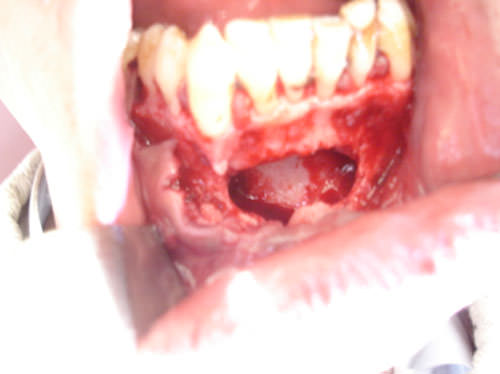

Figura 3

Defecto óseo después de eliminado el quiste. (Caso 1)

Después bajo anestesia local se realiza colgajo vestibular con decolado del mucoperiostio, posteriormente se realiza ostectomía de la cortical ósea externa y se realiza curetaje periapical extenso eliminando el quiste en su totalidad y el trayecto fistuloso que comunicaba el quiste mandibular con la fístula cutánea, para evitar la residiva, seguidamente se lava bien el defecto óseo con suero fisiológico estéril y se reconstruye la cavidad con hidroxiapatita en gránulos HAP-200 realizándose posteriormente plastia de la fístula cutánea. A los siete días se retira la sutura intraoral y extraoral realizando seguimiento clínico-radiográfico donde se observa una buena osteintegración del material al hueso (Figuras 3, 4, 5, 6, 8, 10,11, 12, 13) donde se muestran los pasos del tratamiento.